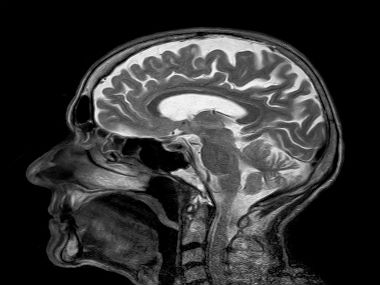

- Most aneurysms get diagnosed accidentally when a person goes for a CT scan, MRI or other tests

A cerebral aneurysm is a condition marked by the ballooning of arteries in certain areas of the brain. These arteries then become weak and prone to rupture - in some cases, this may cause a brain stroke or haemorrhage. According to an estimate, about 3% of the world’s population suffers from the condition, with a higher prevalence among women over 50. When an aneurysm bursts, it leads to subarachnoid haemorrhage (SAH) - in layman’s terms, brain bleeds. SAH accounts for 0.4% to 0.6% of all the deaths in the world, with almost 76,500 to 204,100 new cases in India every year. [caption id=“attachment_7297521” align=“alignleft” width=“380”]  Representational image. Image by toubibe from Pixabay[/caption] Many notable people have suffered from SAH, including the American actress Sharon Stone and Canadian singer and songwriter Neil Young. In March 2019, Game of Thrones actor Emilia Clarke (Daenerys Targaryen) said she had suffered two brain bleeds while shooting the earlier seasons of the show. Here’s a detailed overview of what is a cerebral aneurysm, and why so many cases go undetected until there’s a potentially fatal brain bleed. What causes aneurysms? Though the exact cause of aneurysms is not known yet, experts think they may have something to do with high blood pressure, brain trauma, atherosclerosis (blocked arteries because of cholesterol build-up) or may even be hereditary. There are also many theories about why aneurysm forms. These range from structural fatigue of the arterial walls (which can happen in hypertensive people) to inflammation mediated by the immune system. In a recent study which was done by the University of Sussex in collaboration with the University of Seattle, USA, researchers discovered that some forms of brain aneurysms may be caused due to a genetic mutation in the PDGFRB gene, which is also responsible for various developmental disorders in human beings. Studies have found that a type of anticancer drug-receptoror tyrosine kinase inhibitors - can successfully be used to treat aneurysms. Though drug testing is still in progress, it is something to look forward to as a revolutionary step in identifying and resolving aneurysm causes. What can you do about it? Unruptured aneurysms only present symptoms if they are large enough to press against the brain. Then, they may present in the form of blurred vision, eye pain, headache, facial pain and problems with speaking. Ruptured aneurysms can cause a very sharp and severe headache with stiffness in the neck, light sensitivity and fainting. Since most aneurysms do not show any apparent symptoms — until the person has a stroke — they can be difficult to diagnose. According to the National Institute of Neurological Disorders and Stroke, UK, about 25% people with a ruptured aneurysm die within the first 24 hours or six months due to complications, and those who survive, suffer neurological damage or loss of certain brain functions. Statistics are even worse in India. In ‘Need for brain aneurysm treatment registry of India: How effectively are we treating intracranial aneurysms in India?’, an article published in Neurology India, a publication of the Neurological Society of India, Sudheer Ambekar, a fellow at the University of Miami, said that about 40% aneurysms in India are fatal. We still need a multilevel approach, including a national registry to identify and treat cerebral aneurysm cases effectively, he explained. What are the treatment options? There are limited treatment options for aneurysms today. Treatment usually includes minimally invasive procedures such as endovascular coiling. In this procedure, instead of opening the skull, a coil is introduced into the body through the femoral artery and placed onto the aneurysm to stop the bleeding. Another treatment method is surgical clipping, where the skull is opened to control bleeding from the aneurysm site. A third option is flow diverters that can help to reduce the size of the aneurysm and keep it from bursting. The future, however, looks promising. There’s new research on how to find an aneurysm before it turns fatal. The most recent among these is a tiny device developed by researchers at Stanford University - it uses a deep learning model called the HeadXNet to find possible aneurysms in the brain with a CT scan. If and when they can be used in clinical practice, these devices could have tremendous possibilities for preventing death by bleeding in the brain. This article was created by myUpchar, India’s first and biggest online resource for verified medical information. For more in-depth information on all things health, please visit www.myupchar.com/en. For more details on this topic, please see: https://www.myupchar.com/en/disease/brain-aneurysm